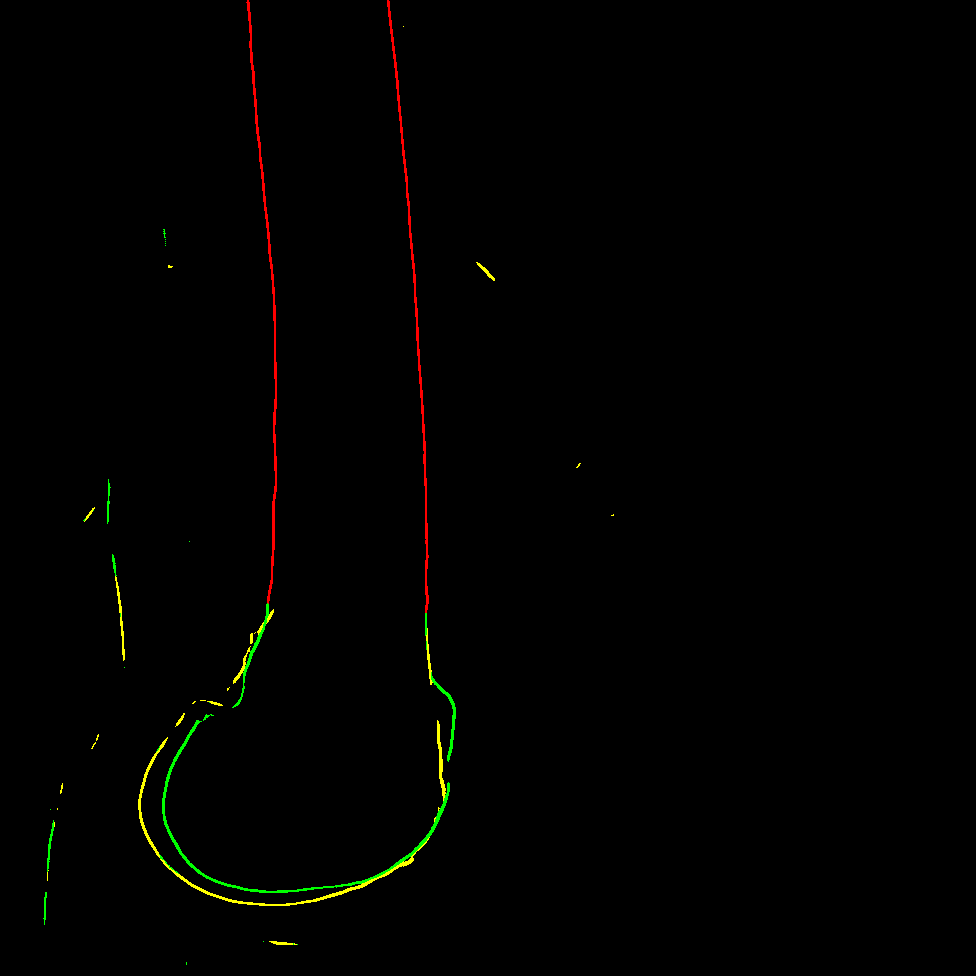

The key idea behind our contour-based ICP registration method is to achieve accurate 2D/3D matches using component-level contours instead of object-level ones. This raises the question of how to define component classes based on the anatomy of the femur. Although X-rays are transparent, for the sake of clarity, we assume the femur to be an opaque object for now and focus specifically on its occluding contours, which appear in the X-ray as sudden changes in tissue density. We recall that for an occluding contour to form, the shape must be locally convex in the viewing direction. In other words, at the point where the occluding contour is observed, the surface of the object must curve outward toward the observer.

Based on this definition, we propose dividing the femur into three convex substructures, each associated with a contour category, that are convex with respect to an observer (the C-arm) rotating around the diaphysis’s main axis: diaphysis, the medial condyle and the lateral condyle (shown Figure 1) of class indices in the following.

In this section we want to give a visual explanation of our contour matching. Unlike registration methods relying on object-level contours (see Figure 8, left), we propose extracting component-level contours, specifically those of anatomical substructures (see Figure 8, right).